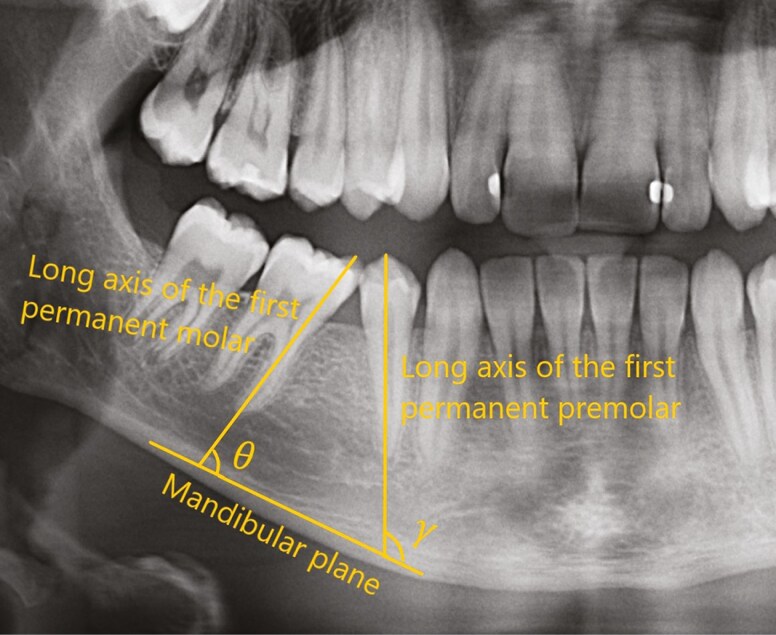

Materials and methods: Patients with bilateral agenesis of the second mandibular molars and unerupted second molars were included and randomly allocated to either extraction or hemisection on the left or right side of the mandible. Clinical and radiographic examinations were conducted at baseline (T1) and after a mean follow-up period of 4.2 years (T2). Measurements of the residual spaces and tooth angulation of the mandibular first molar and premolar following extraction were blinded assessed on panoramic radiographs and cast models. The number of visits, chair time, social costs, and direct and indirect costs were calculated using cost minimisation analysis.

Results: A total of 40 patients (25 boys and 15 girls) with a mean age of 10.03 ± 1.07 years at T1 participated. No patient was lost to follow-up. The residual space between the first permanent molar and the first permanent premolar was 2.04 ± 1.67 mm for hemisection and 2.39 ± 1.86 mm for extraction (p = 0.053). A larger residual space was observed between the first permanent premolar and the canine on the hemisection side (1.80 ± 1.01 mm) than on the extraction side (1.55 ± 0.92 mm), (p = 0.045). No difference was found between the interventions regarding the angulation of the first permanent molar (p = 0.0914) or the angulation of the first permanent premolar (p = 0.7812). Hemisection resulted in significantly more complications (p = 0.0176) and was associated with substantially higher material costs, more chair time and higher indirect costs than conventional extraction (p < 0.0001).